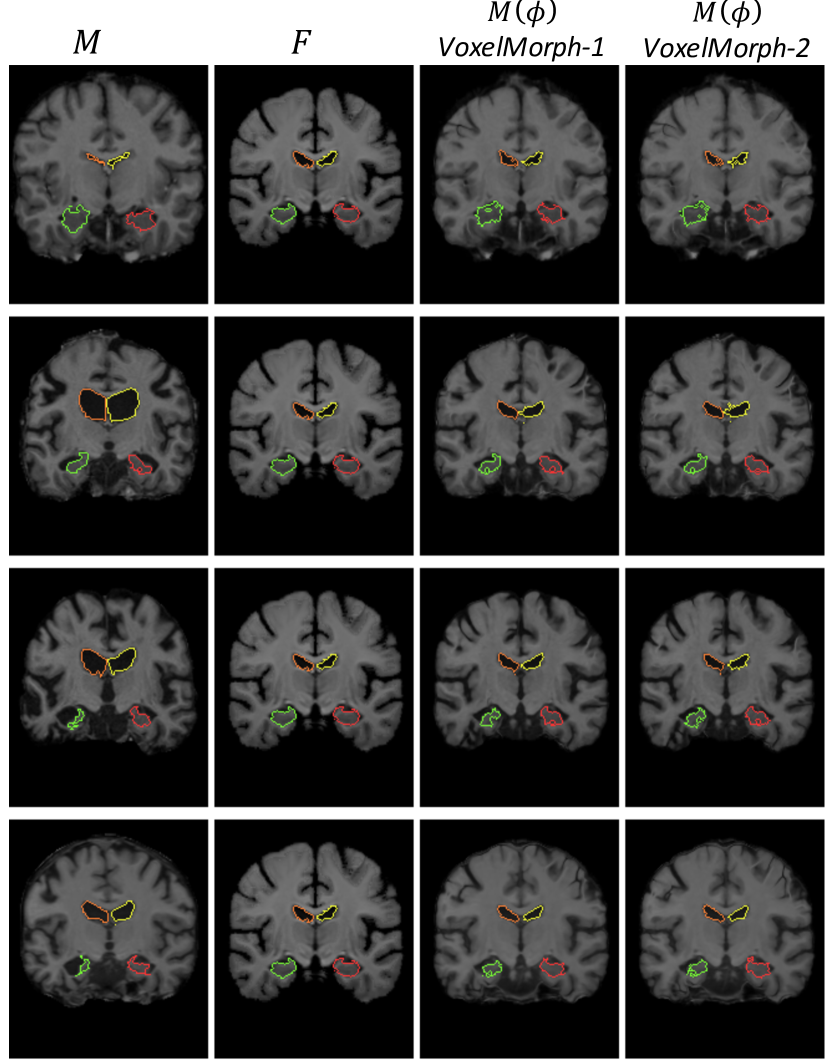

We focus on atlas-based registration, in which we compute a registration field between an atlas, or reference volume, and each volume in our dataset. Atlas-based registration is a common formulation in population analysis, where inter-subject registration is a core problem. The atlas represents a reference, or average volume, and is usually constructed by jointly and repeatedly aligning a dataset of brain MR volumes and averaging them together. We use an atlas computed using an external dataset [17, 40]. Each input volume pair consists of the atlas (image F𝐹F) and a random volume from the dataset (image M𝑀M). Columns 1-2 of Fig. 4 show example image pairs from the dataset using the same fixed atlas for all examples. All figures that depict brains in this paper show 2D coronal slices for visualization purposes only. All registration is done in 3D.

Refer to caption

Figure 4: Example MR coronal slices extracted from input pairs (columns 1-2), and resulting M(ϕ)𝑀italic-ϕM(\phi) for VoxelMorph-1 and VoxelMorph-2, with overlaid boundaries of the ventricles (yellow, orange) and hippocampi (red, green). A good registration will cause structures in M(ϕ)𝑀italic-ϕM(\phi) to look similar to structures in F𝐹F. Our networks handle large changes in shapes, such as the ventricles in row 2 and the left hippocampi in rows 3-4.